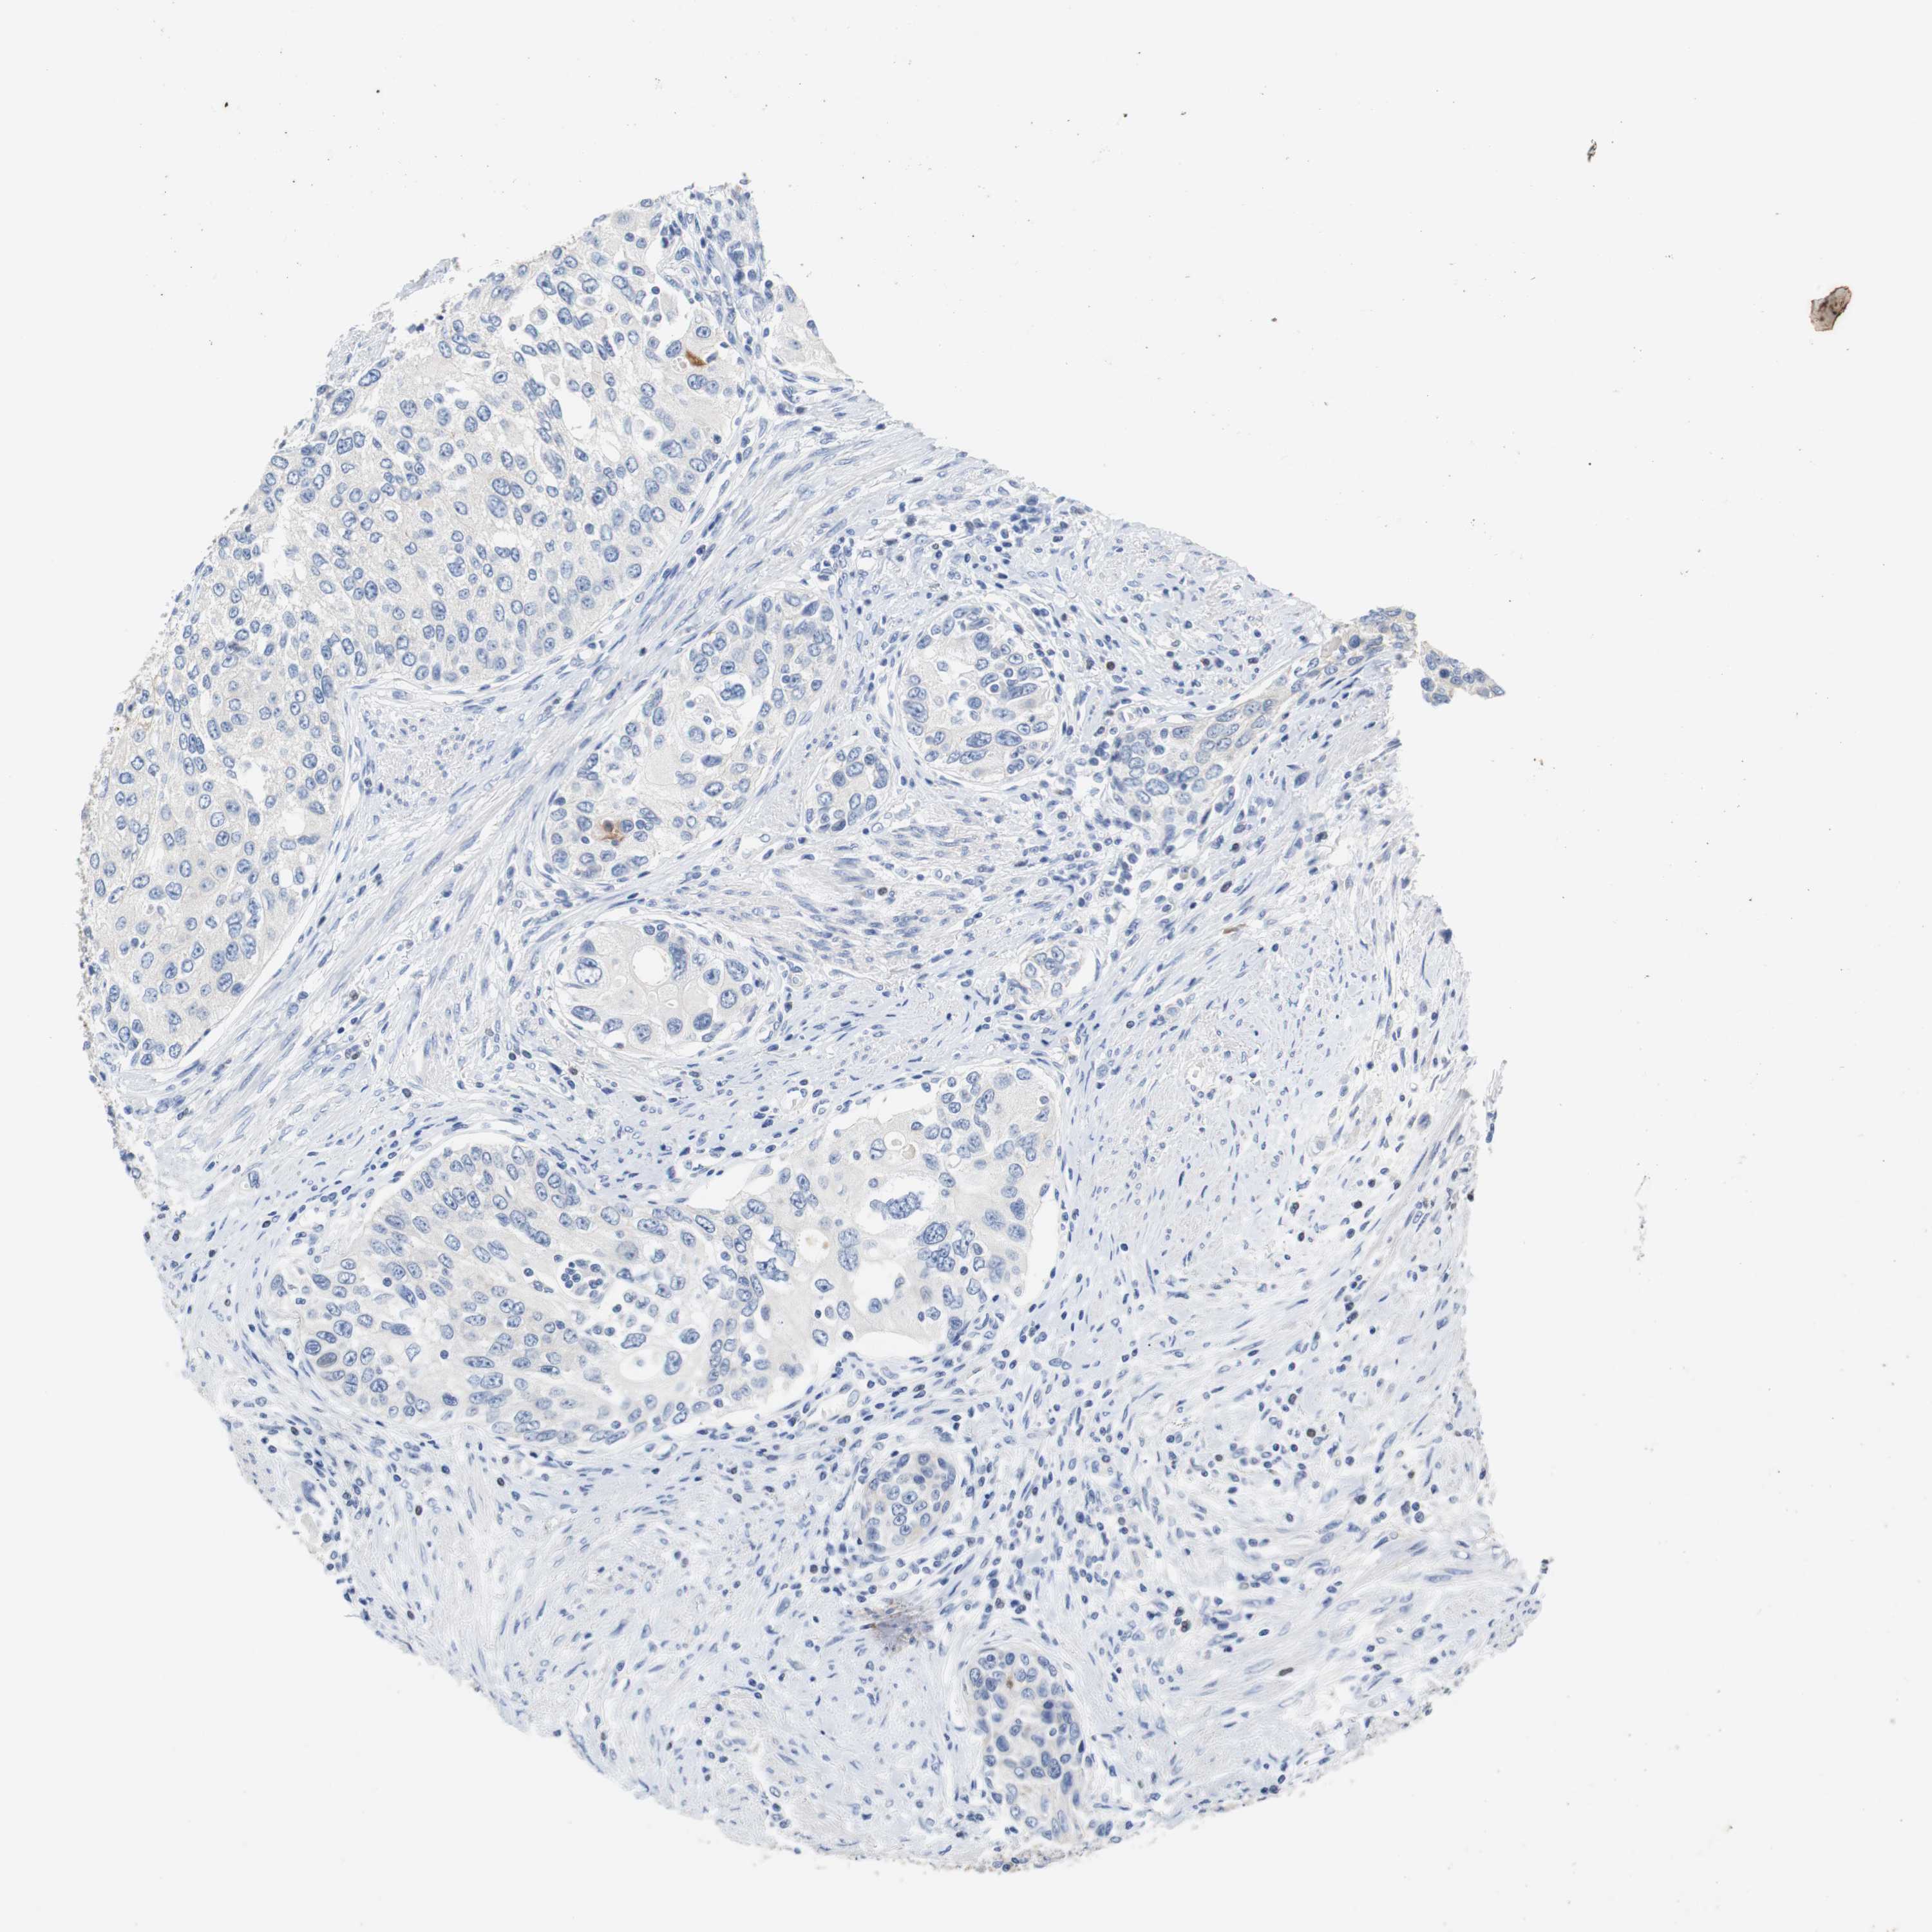

UROTHELIAL CANCER - Protein expressioni

A mouse-over function shows sample information and annotation data. Click on an image to view it in a full screen mode. Samples can be filtered based on level of antibody staining by selecting one or several of the following categories: high, medium, low and not detected. The assay and annotation is described here.

Note that samples used for immunohistochemistry by the Human Protein Atlas do not correspond to samples in the TCGA dataset.

Antibody stainingi

Antibody staining in the annotated cell types in the current human tissue is reported as not detected, low, medium, or high, based on conventional immunohistochemistry profiling in selected tissues. This score is based on the combination of the staining intensity and fraction of stained cells.

Each image is clickable and will lead to virtual microscopy that enables deeper exploration of all samples and also displays staining intensity scores, fraction scores and subcellular localization as well as patient and tissue information for each sample.

Antibody HPA006277

Antibody HPA006507

Antibody CAB017027

Staining

High

Medium

Low

Not detected

Intensity

Strong

Moderate

Weak

Negative

Quantity

>75%

75%-25%

<25%

None

Location

Nuclear

Cytoplasmic/membranous

Cytoplasmic/membranous,nuclear

Urothelial carcinoma, Low grade

Urothelial carcinoma, High grade